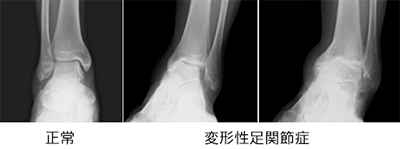

変形性足関節症は、加齢やケガ、炎症など、いろいろな原因により足首の関節の軟骨がすり減った状態です。軟骨が消失し骨と骨が直接こすれあうようになり、痛みや機能障害が増大していきます。

放置していると、通常加齢とともに、軟骨の摩耗が進行し、変形が進行し、痛みと関節の動きも悪化します。

治療は、程度が軽度なら消炎鎮痛剤、関節内注射、装具、リハビリなどの保存治療が有効です。

しかし、変形の強い変形性足関節症では、長期にわたり、痛みを確実に取り除くために、手術療法が必要となります。手術療法は関節固定術や関節温存手術、人工関節などがあります。我々は、リング型創外固定を使用した骨切り術による関節温存手術を積極的に行っています。末期の変形性関節症の方に対して関節固定術においても、関節鏡を用いた方法を行うことで侵襲を小さくする方法を行っています。また患者さんの状態に応じて、人工関節手術も行っています。